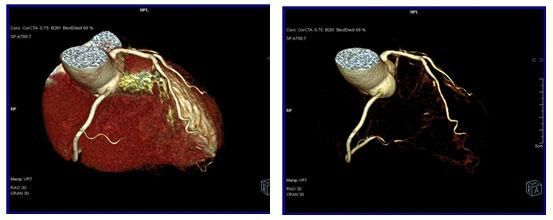

64排螺旋CT冠狀動脈血管成像:

1、簡單:無需經動脈插管,隻需象平時靜脈輸液一樣在肘靜脈内推注相對适量對比劑,然後行快速掃描即可完成整個檢查。

2、安全:64排螺旋CT冠狀動脈造影,對比劑用量較少,無需動脈插入導管,患者無需承擔麻醉及動脈插管等帶來并發症的危險。在冠狀動脈血管疾病的篩查、早期診斷、冠狀動脈成形術和搭橋術前、術後血管評價,冠狀動脈起源異常及心肌橋等方面極具優勢。

3、後處理功能豐富:西門子公司爲SOMATOM Definition AS+ 128層4D螺旋CT配備了功能強大的後處理工作站:MMWP(多産品工作站)和最新型的醫學影像IT工作平台,Syngo.via,智能,便捷。

CT冠脈血管成像: